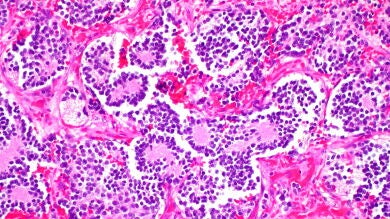

El neuroblastoma es un tipo de cáncer que se inicia en las células llamadas neuroblastos, un tipo de células nerviosas inmaduras que se encuentran en diferentes órganos del cuerpo.

Los neuroblastos no son malos ni tienen un destino tumoral inequívoco. De hecho, son imprescindibles en la vida. Durante nuestro desarrollo embrionario, los neuroblastos proliferan y migran, dando origen al sistema nervioso central y periférico. Solo cuando se reproducen de forma incontrolada, es cuando pueden generar tumores como el neuroblastoma.

El problema es que no solo afecta a las células inmaduras, también a las vidas que recién se inician: suele afectar a los niños de 5 años o menos. Tanto que es el tumor más frecuente durante los 2 primeros años de vida y, después de los tumores del sistema nervioso central como conjunto, el tumor sólido más frecuente del niño. En total representa el 8-10% de los tumores pediátricos. Su incidencia estimada es de 1 por cada 70.000 recién nacidos vivos, lo que en España supone unos 100 casos al año, según datos de la Fundación Neuroblastoma.